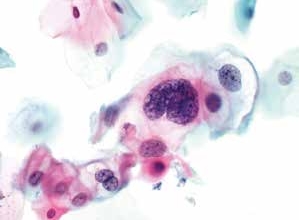

图4-15 低度鳞状上皮内病变(LSIL)合并单纯疱疹病毒感染(HSV)(高倍、液基、巴氏染色)

细胞核增大,异型性明显,核周空腔,为典型的挖空细胞(红箭头)。同时还可见疱疹病毒感染而导致的细胞改变(黄箭头)。此例为LSIL合并HSV感染。